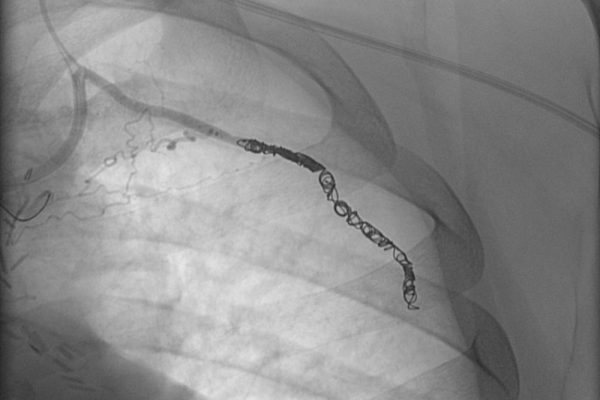

Συνοπτικά υπό την καθοδήγηση του αγγειογράφου, αναγνωρίζεταιτο παθολογικό αγγείο-αγγεία και με ειδικούς καθετήρες και μικροκαθετήρες, διοχετεύονται εμβολικά υλικάόπως μικροσφαιρίδια ή coils, ώστε να αποφραχθεί ή να μειωθεί η παθολογική αγγείωση.